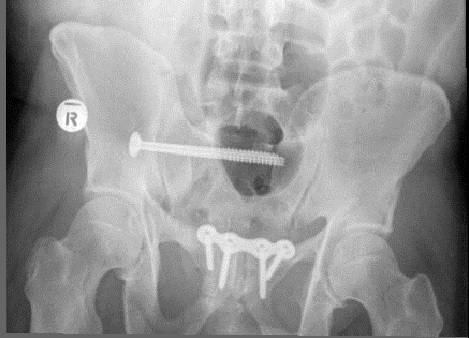

Fig1. - 'Open book' fracture of the pelvis.

Fig1. - Treated with open reduction and internal fixation.